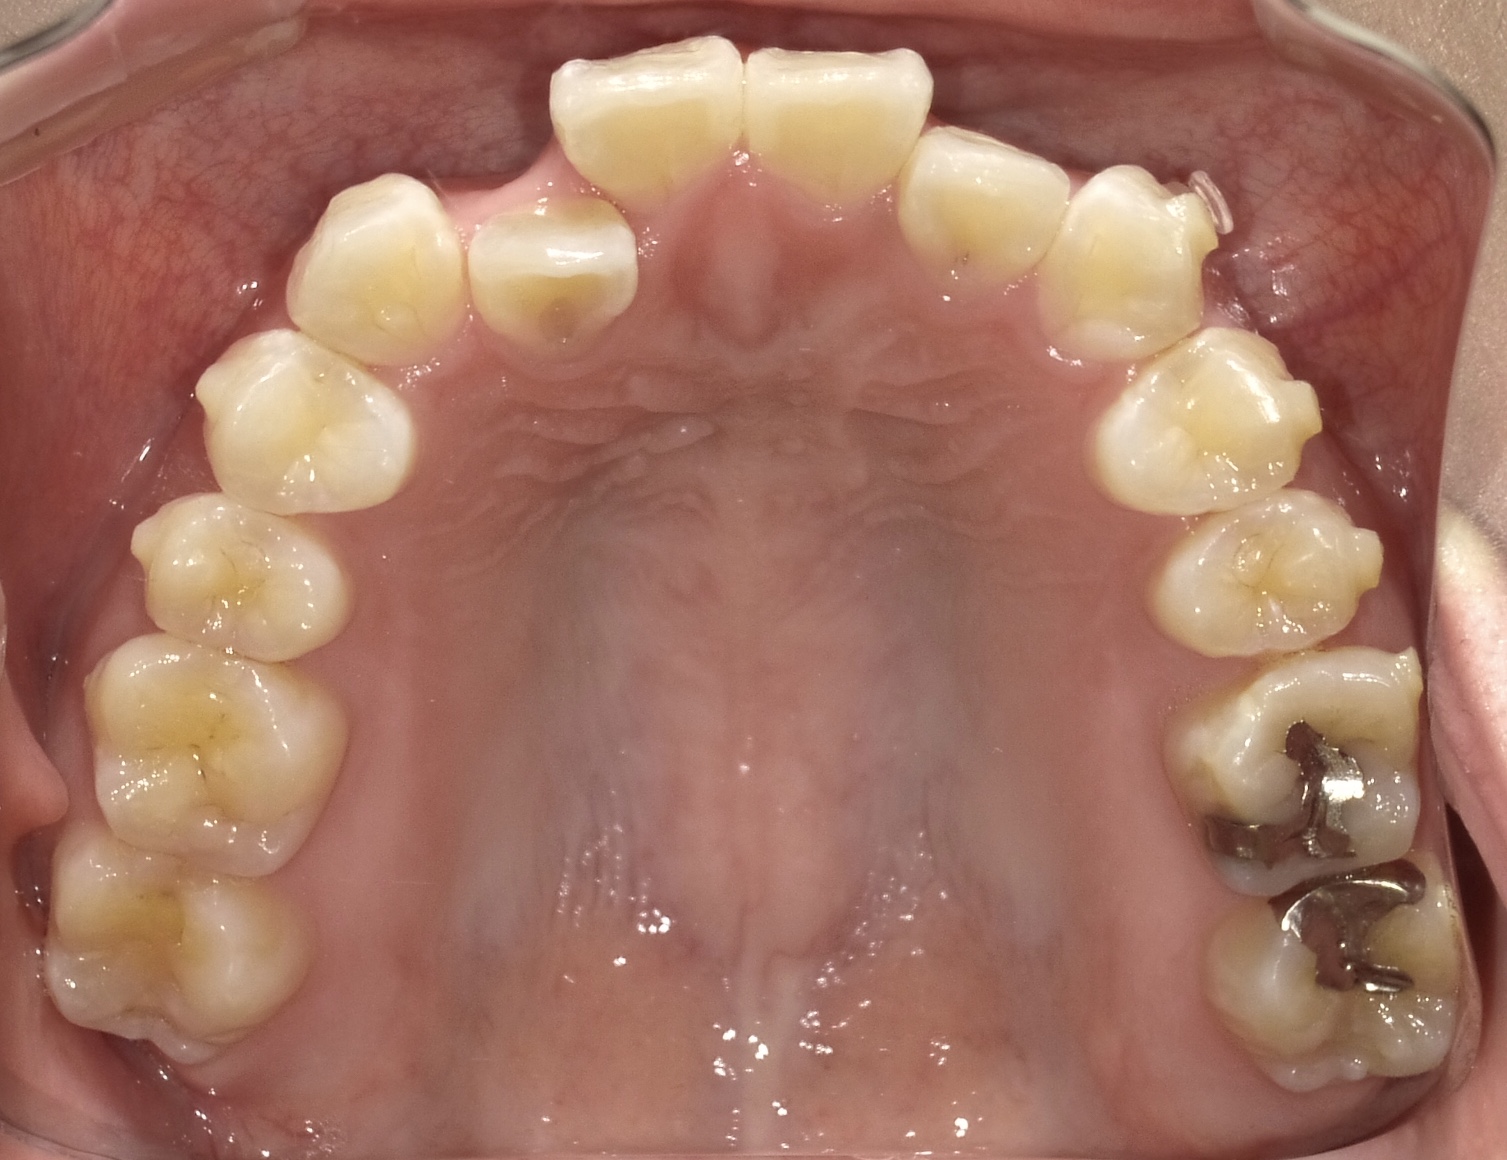

矯正スタート時(上顎)撮影:2018.07↓ 矯正9ヶ月経過(上顎)撮影:2019.04↓

上顎はまだまだ時間がかかりそうです…😢

前歯の隣の歯(2番)は左右どちらも少しですが前に出てきた気がします!